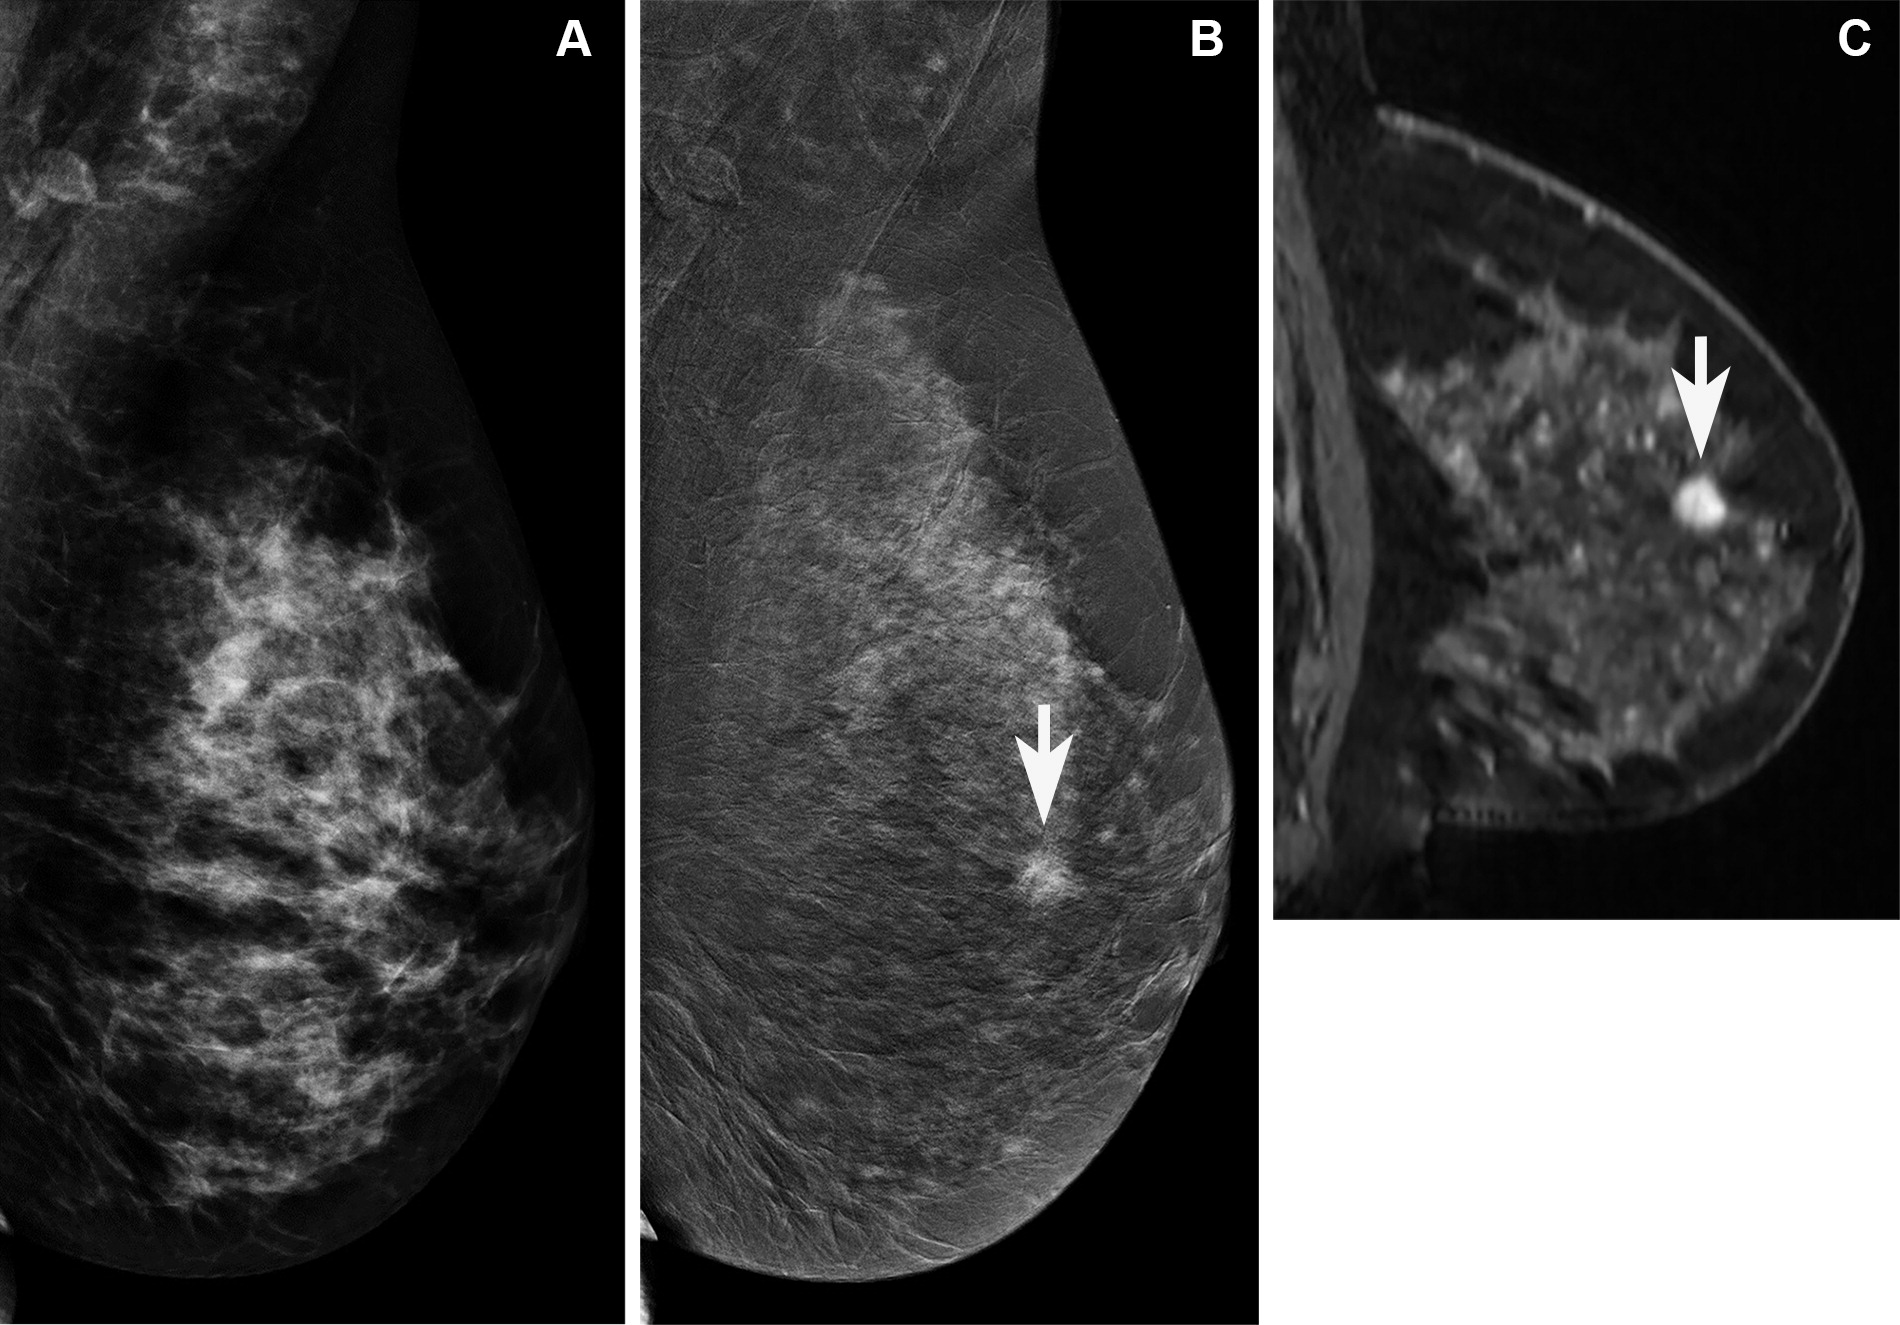

A team led by Marissa Lawson, MD, from the University of Washington in Seattle found that abbreviated breast MRI had comparable performance to standard MRI. Meanwhile, CEM had lower recall and higher specificity compared to both MRI methods but also had lower cancer detection rate and sensitivity.

The researchers found that while abbreviated MRI showed no significant differences in performance metrics with standard MRI, CEM varied in performance.

Additionally, the authors wrote that while their meta-analyses did not report lesion characteristics, these may have impacted CEM's sensitivity in their study. They called for future studies with larger sample sizes to investigate CEM's tradeoffs, as well as patient acceptance.

"In addition, our MRI protocol has spatial resolution that exceeds [ACR] accreditation standards, which likely facilitates superior depiction of lesions compared with CEM," the authors wrote.